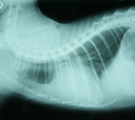

初診時胸部X線所見。心陰影拡大とスリガラス陰影あり。 第8病日さらに心陰影拡大し、心嚢液貯留が疑われた。 同日血膿様液を154ml抜去し、Pasteurella属を検出した。 退院2ヶ月後の胸部X線所見。心陰影正常で再発していない。

経過:初診時、体温:39.1℃ 心拍数:200/分 呼吸数:68/分。可視粘膜色良好。食欲元気なし。咳なし。聴診にて心音遠く感じられた。心雑音なし。肺音粗励。胸部X線にて心陰影拡大、気管分岐部挙上、肺野スリガラス陰影が認められた。動脈血ガス分析にてpH7.416, Pco2 27.3 mmHg, Po2 96.4mmHgと肺機能は保たれていた。心嚢液貯留と心機能低下による間質性肺水腫を疑い、利尿剤投与を始めた。翌日、スリガラス影は消失した。第8病日、さらに心陰影が拡大していたので、全身麻酔下、気管内挿管下にて心嚢液の試験穿刺を行った。麻酔前のCBC生化学検査ではWBC 11000/μLで左方移動認めず、ALB2.2g/dlと低下していた。伏臥位にて、透視下に22G静脈留置針を用い右第6肋間を穿刺した。計154mlの血膿様液(Ht9%, WBC>99900/μL, TP5.0g/dl)が抜去された。上清は黄色透明で比重1.033、TP5.0と滲出性、沈渣細胞診にて多数の変性好中球がみられた。培養にてPasteurella属の細菌が検出され、ABPC, AMPC, CEZ, EM, GM,AMK, MINO, OFLX, ENX, FOMに感受性を示した。由来は不明だが、化膿性心嚢液が貯留していたことが判明した。入院管理となりABPC20mg/kgとGM5mg/kgの投与を開始した。第12病日再び19mlの血膿様液を抜去したが培養にて菌は検出されなかった。それ以降心嚢液の再貯留を認めなかった。第22病日経過良好のめ退院。自宅ではバイトリル錠25mgを毎日投与してもらった。その後1ヶ月ごとに3ヶ月間継続して胸部X線心陰影を経過観察したが、再発を認めなかった。